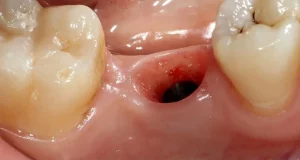

Can You Drink Alcohol After a Tooth Extraction? (9 Safety Tips)

No. You should not drink alcohol after a tooth extraction. The American Dental Association (ADA) recommends avoiding alcohol...